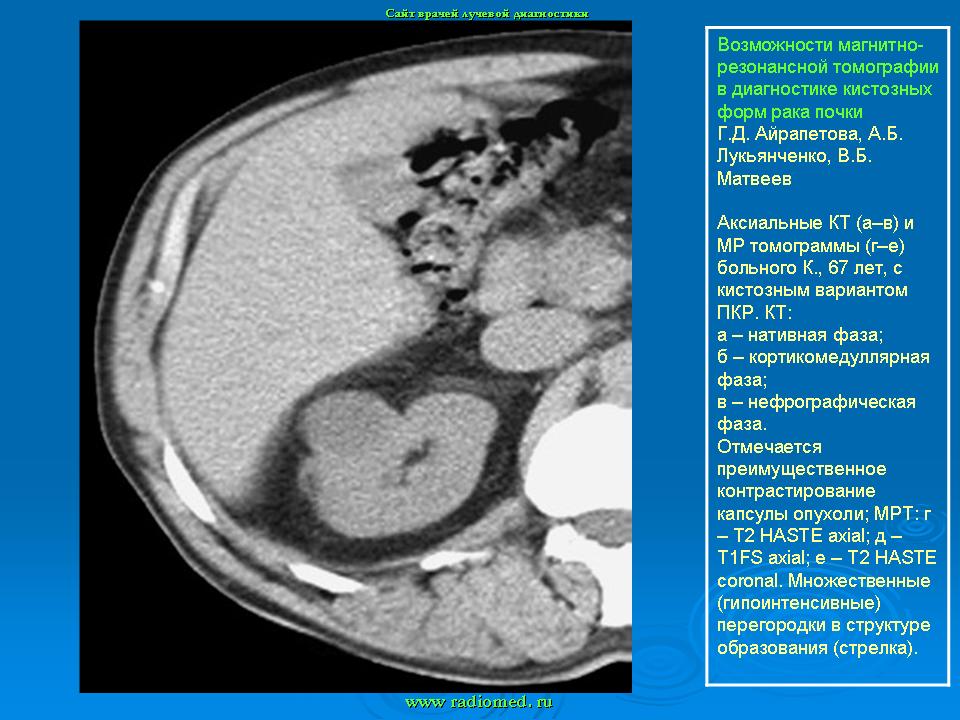

МРТ. Почки и мочевыводящие пути.